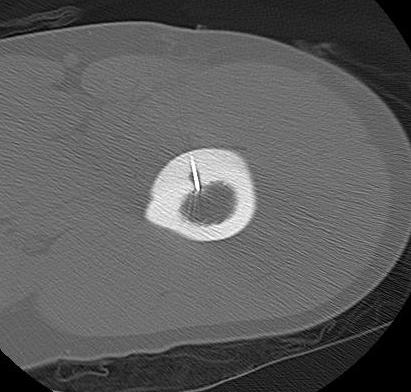

CT

Best investigation

- lucent nidus surrounded by dense bone

Osteoid osteoma tibia

Osteoid osteoma femur